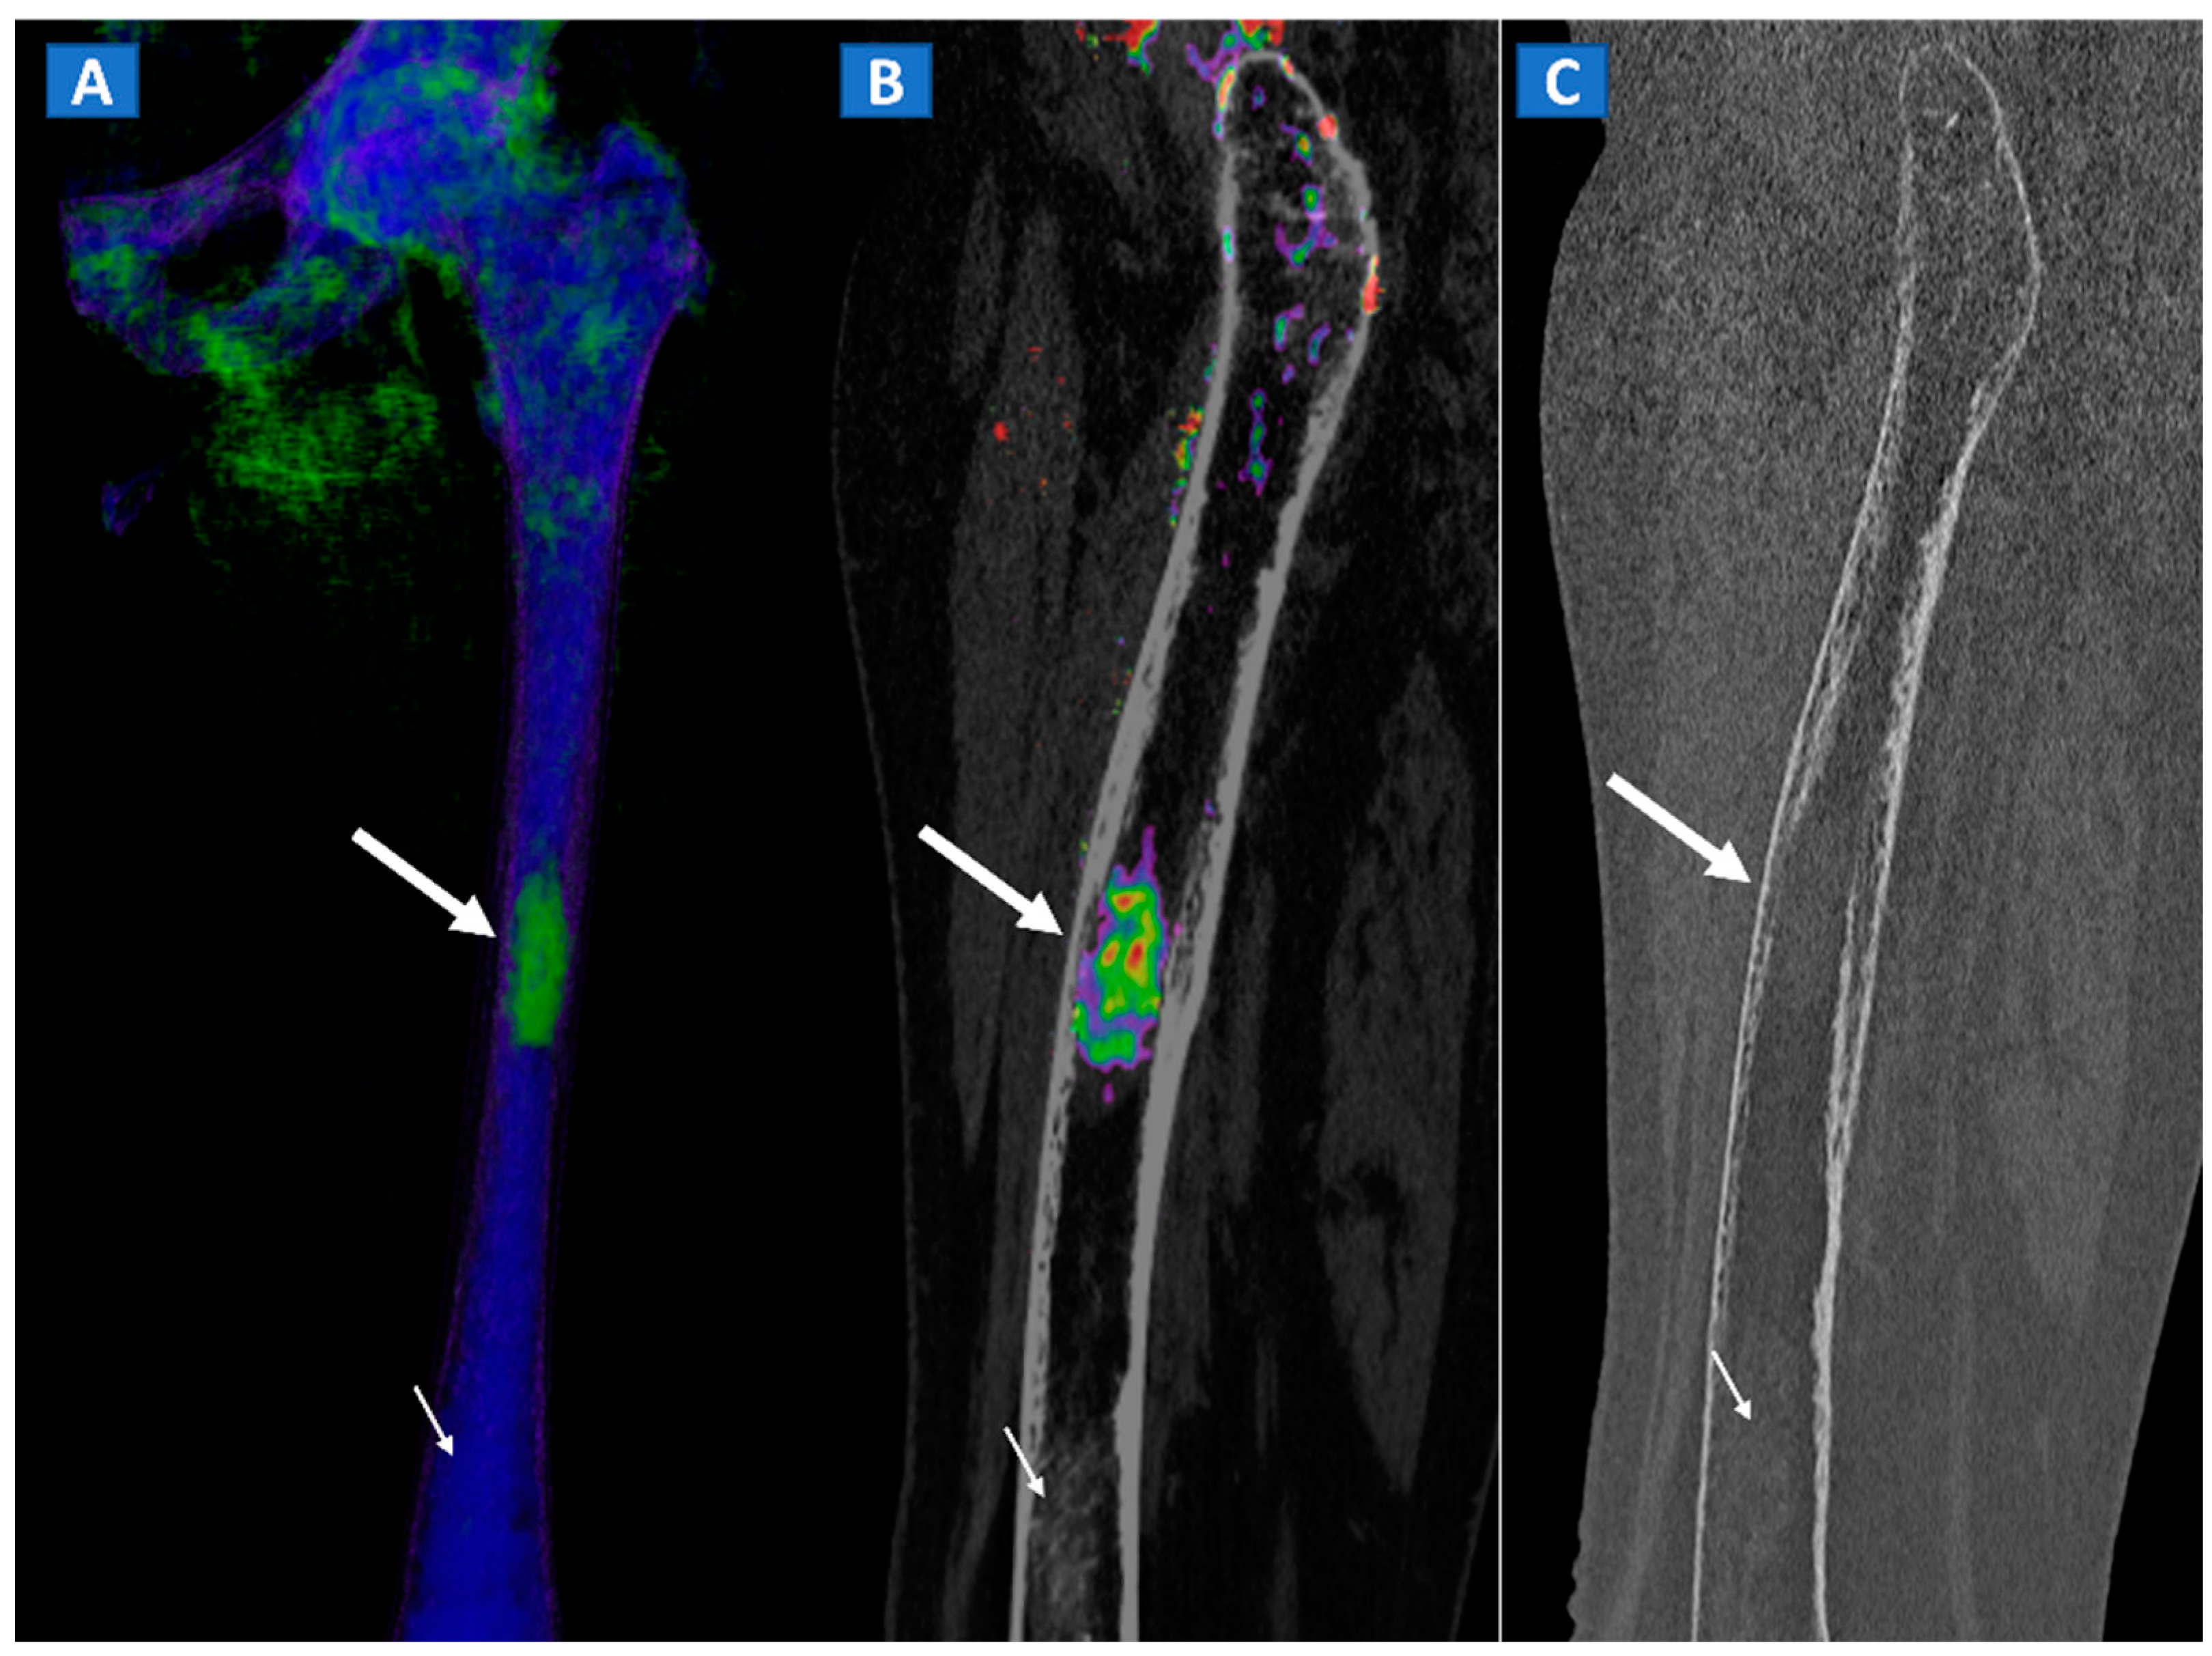

Figure 11.

A 49-year-old female with single occult femoral metastasis from breast cancer. On the 3D DECT image (A) a focal area of edema can be clearly recognized on the left femur (thick arrow). On the para-sagittal 2D image, the lesion (thick arrow) is confirmed on the super-imposed BME map (B). The lesion (thick arrow) is not recognized on the para-sagittal 2D bone window image (C), showing only a non-specific mildly hyperdense pattern, present also on distal femur (thin arrow), and not associated with BME on the DECT images.